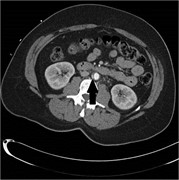

Blunt traumatic infrarenal aortic intimal flap progressing to pseudoaneurysm over 3 months

John Alfred Carr

Journal of Surgical Case Reports, Volume 2016, Issue 6, June 2016, rjw099, https://doi.org/10.1093/jscr/rjw099